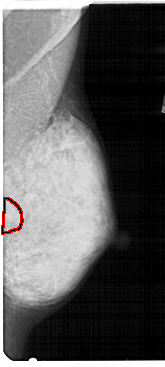

A_1807_1.RIGHT_CC

RIGHT_CC LINES 4801 PIXELS_PER_LINE 2161 BITS_PER_PIXEL 12 RESOLUTION 43.5 OVERLAY

FILE: A_1807_1.RIGHT_CC.OVERLAY

TOTAL_ABNORMALITIES 1

ABNORMALITY 1

LESION_TYPE CALCIFICATION TYPE PLEOMORPHIC DISTRIBUTION CLUSTERED

ASSESSMENT 4

SUBTLETY 2

PATHOLOGY BENIGN

TOTAL_OUTLINES 1

BOUNDARY